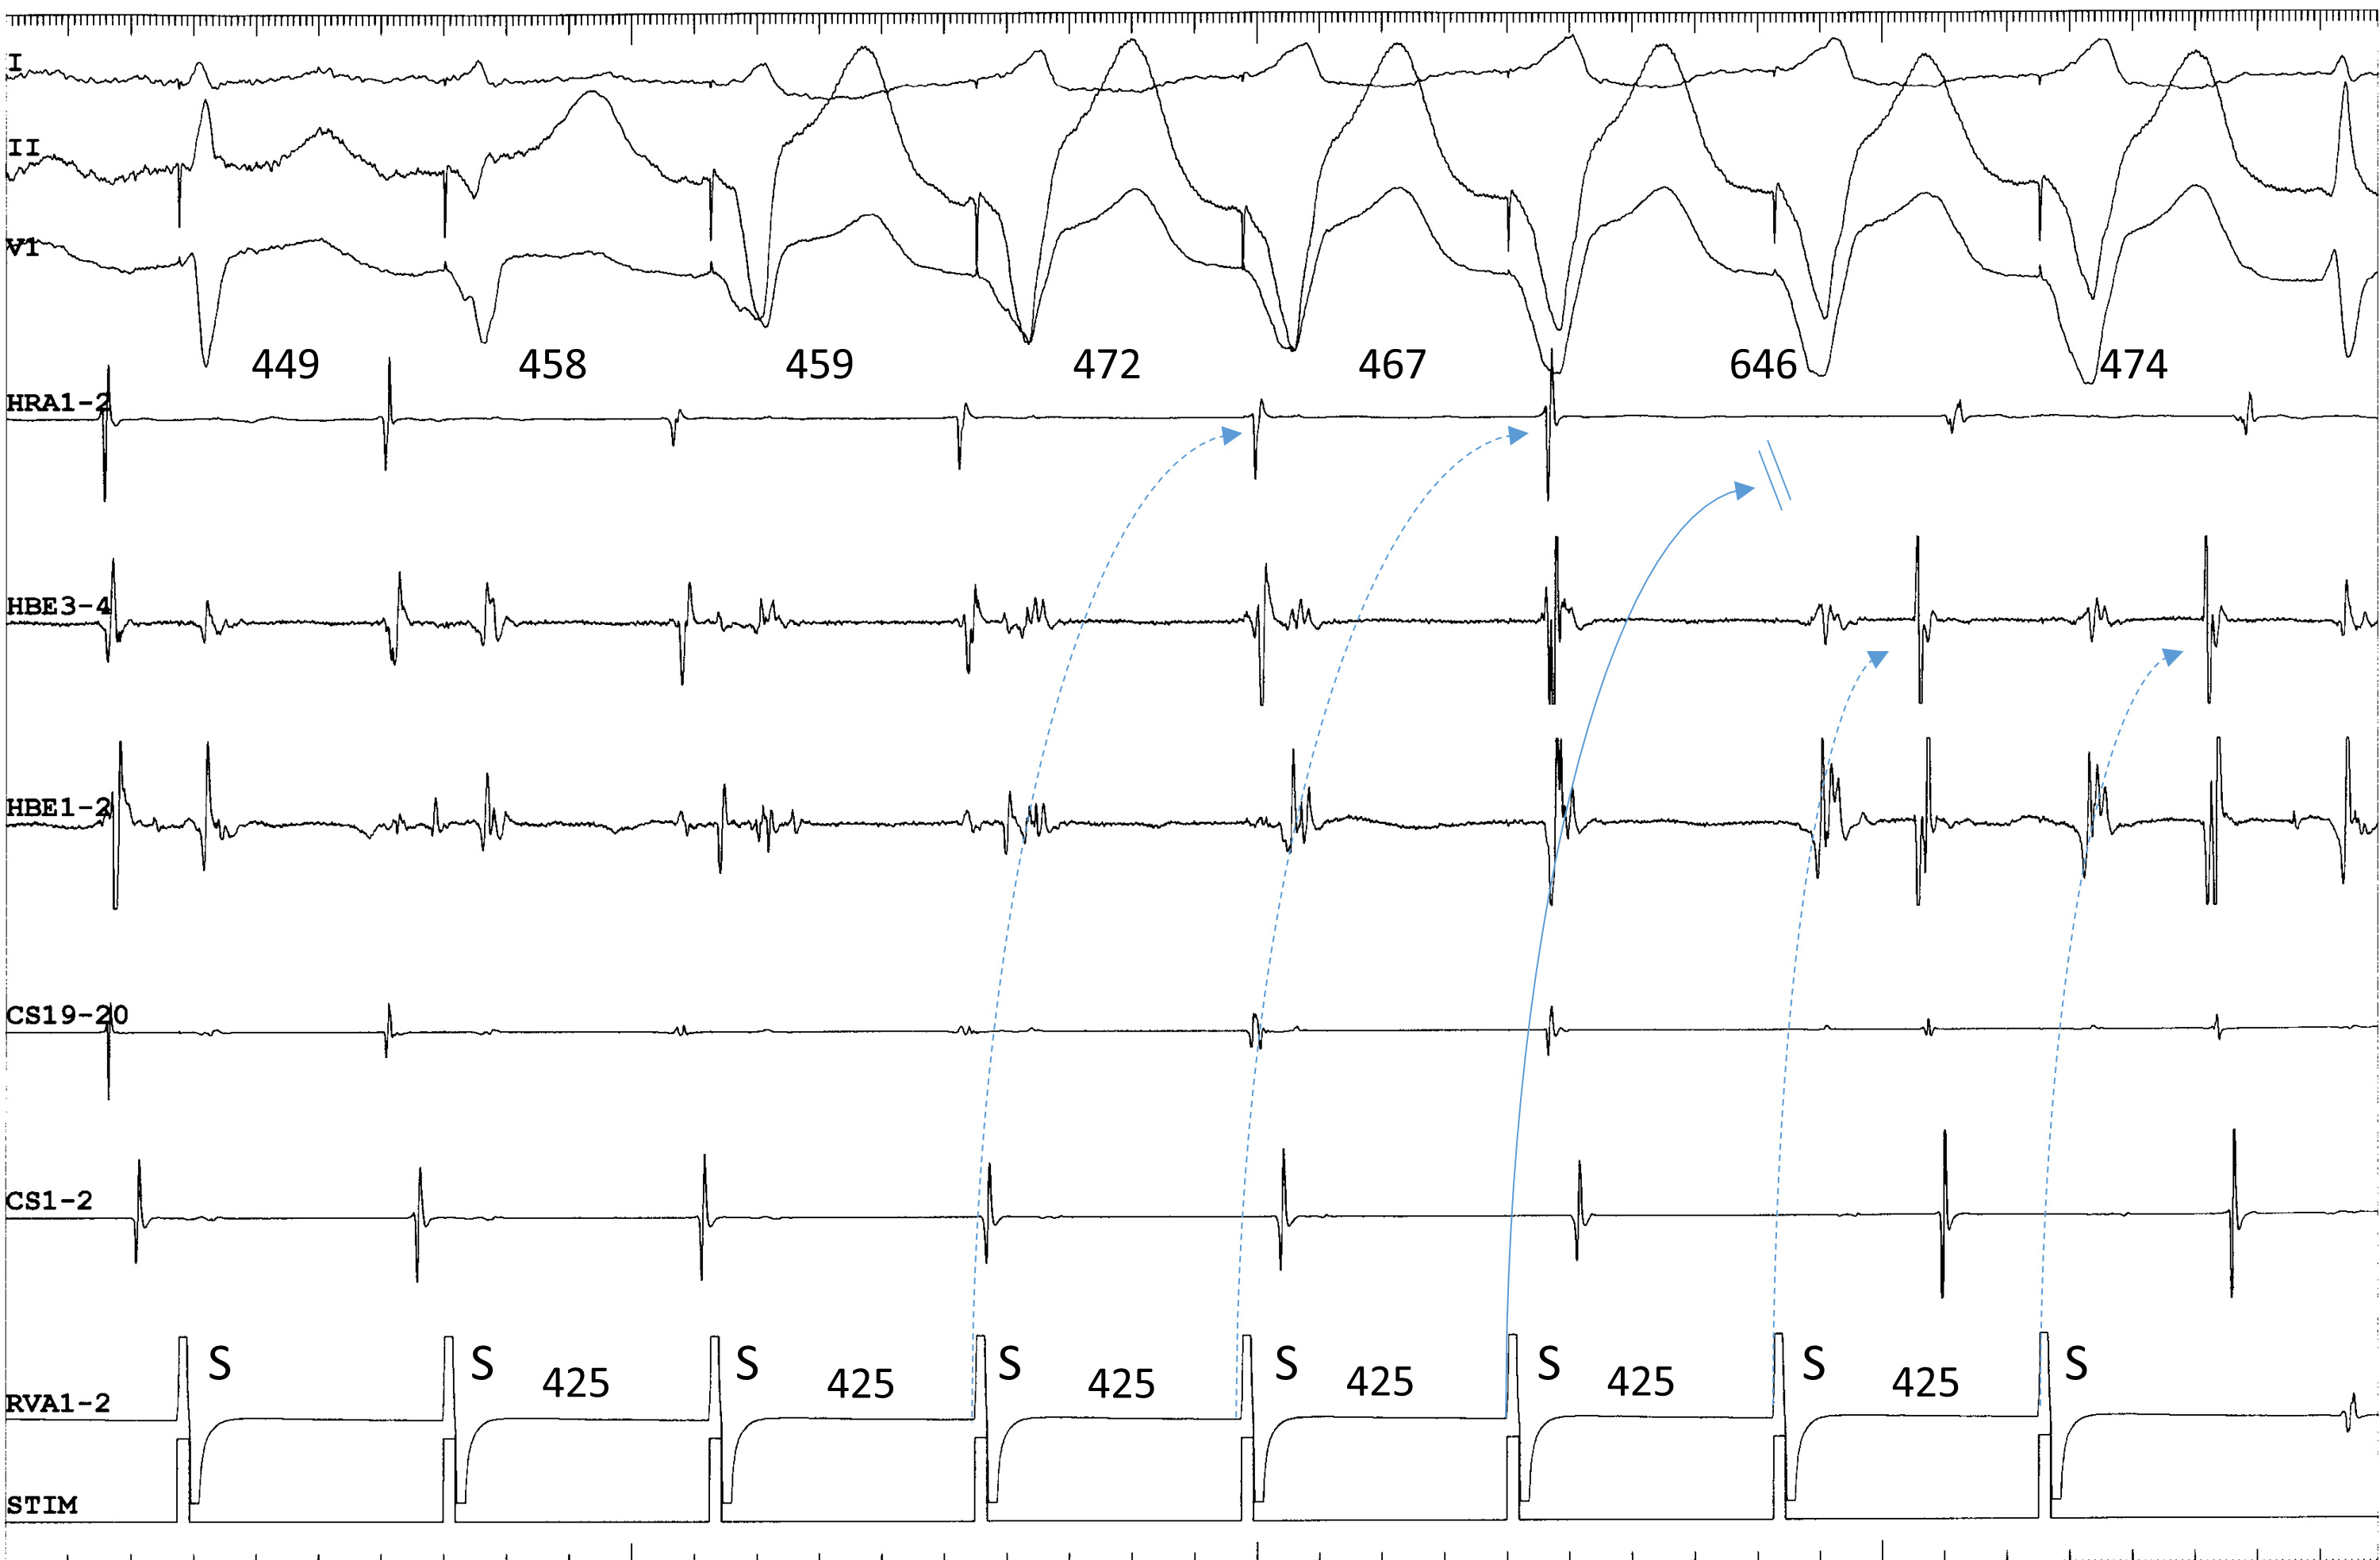

Fig. 2.Termination of fast-slow AVNRT using a superoanterior SP during

ventricular overdrive pacing at an S-S cycle length of 425 ms from the right

ventricular apex (RVA1-2). The site of earliest atrial activation during

tachycardia is recorded in the HRA (HRA1-2). The atrial cycle length immediately

after the 4th and 5th stimuli lengthens slightly without change in the atrial

activation sequence, consistent with an orthodromic capture of the atria over the

superoanterior SP, with a decremental delay in response to the 4th and 5th

stimuli (dotted arrows). The 6th stimulus is blocked (straight arrow), evidenced

by the absence of retrograde activation over the SP in its wake. In response to

the 6th and 7th ventricular stimuli, the site of earliest retrograde atrial

activation was observed in the distal electrogram of the His bundle region

(HBE1-2) along with a short ventriculoatrial interval, consistent with retrograde

conduction over a FP. The numbers above the HRA1-2 channel are the interatrial

intervals. I, II and V

Third, when the tachycardia is terminated by ventricular overdrive pacing, the atrial cycles immediately before the termination may lengthen transiently, due to repetitive retrograde conduction with a decremental delay over the superior SP, followed by orthodromic block inside the superior SP (Fig. 2). This is not simple ventricular entrainment nor termination without atrial capture, but a frequently observed, confirmatory, diagnostic phenomenon which excludes the diagnosis of atrial tachycardia.